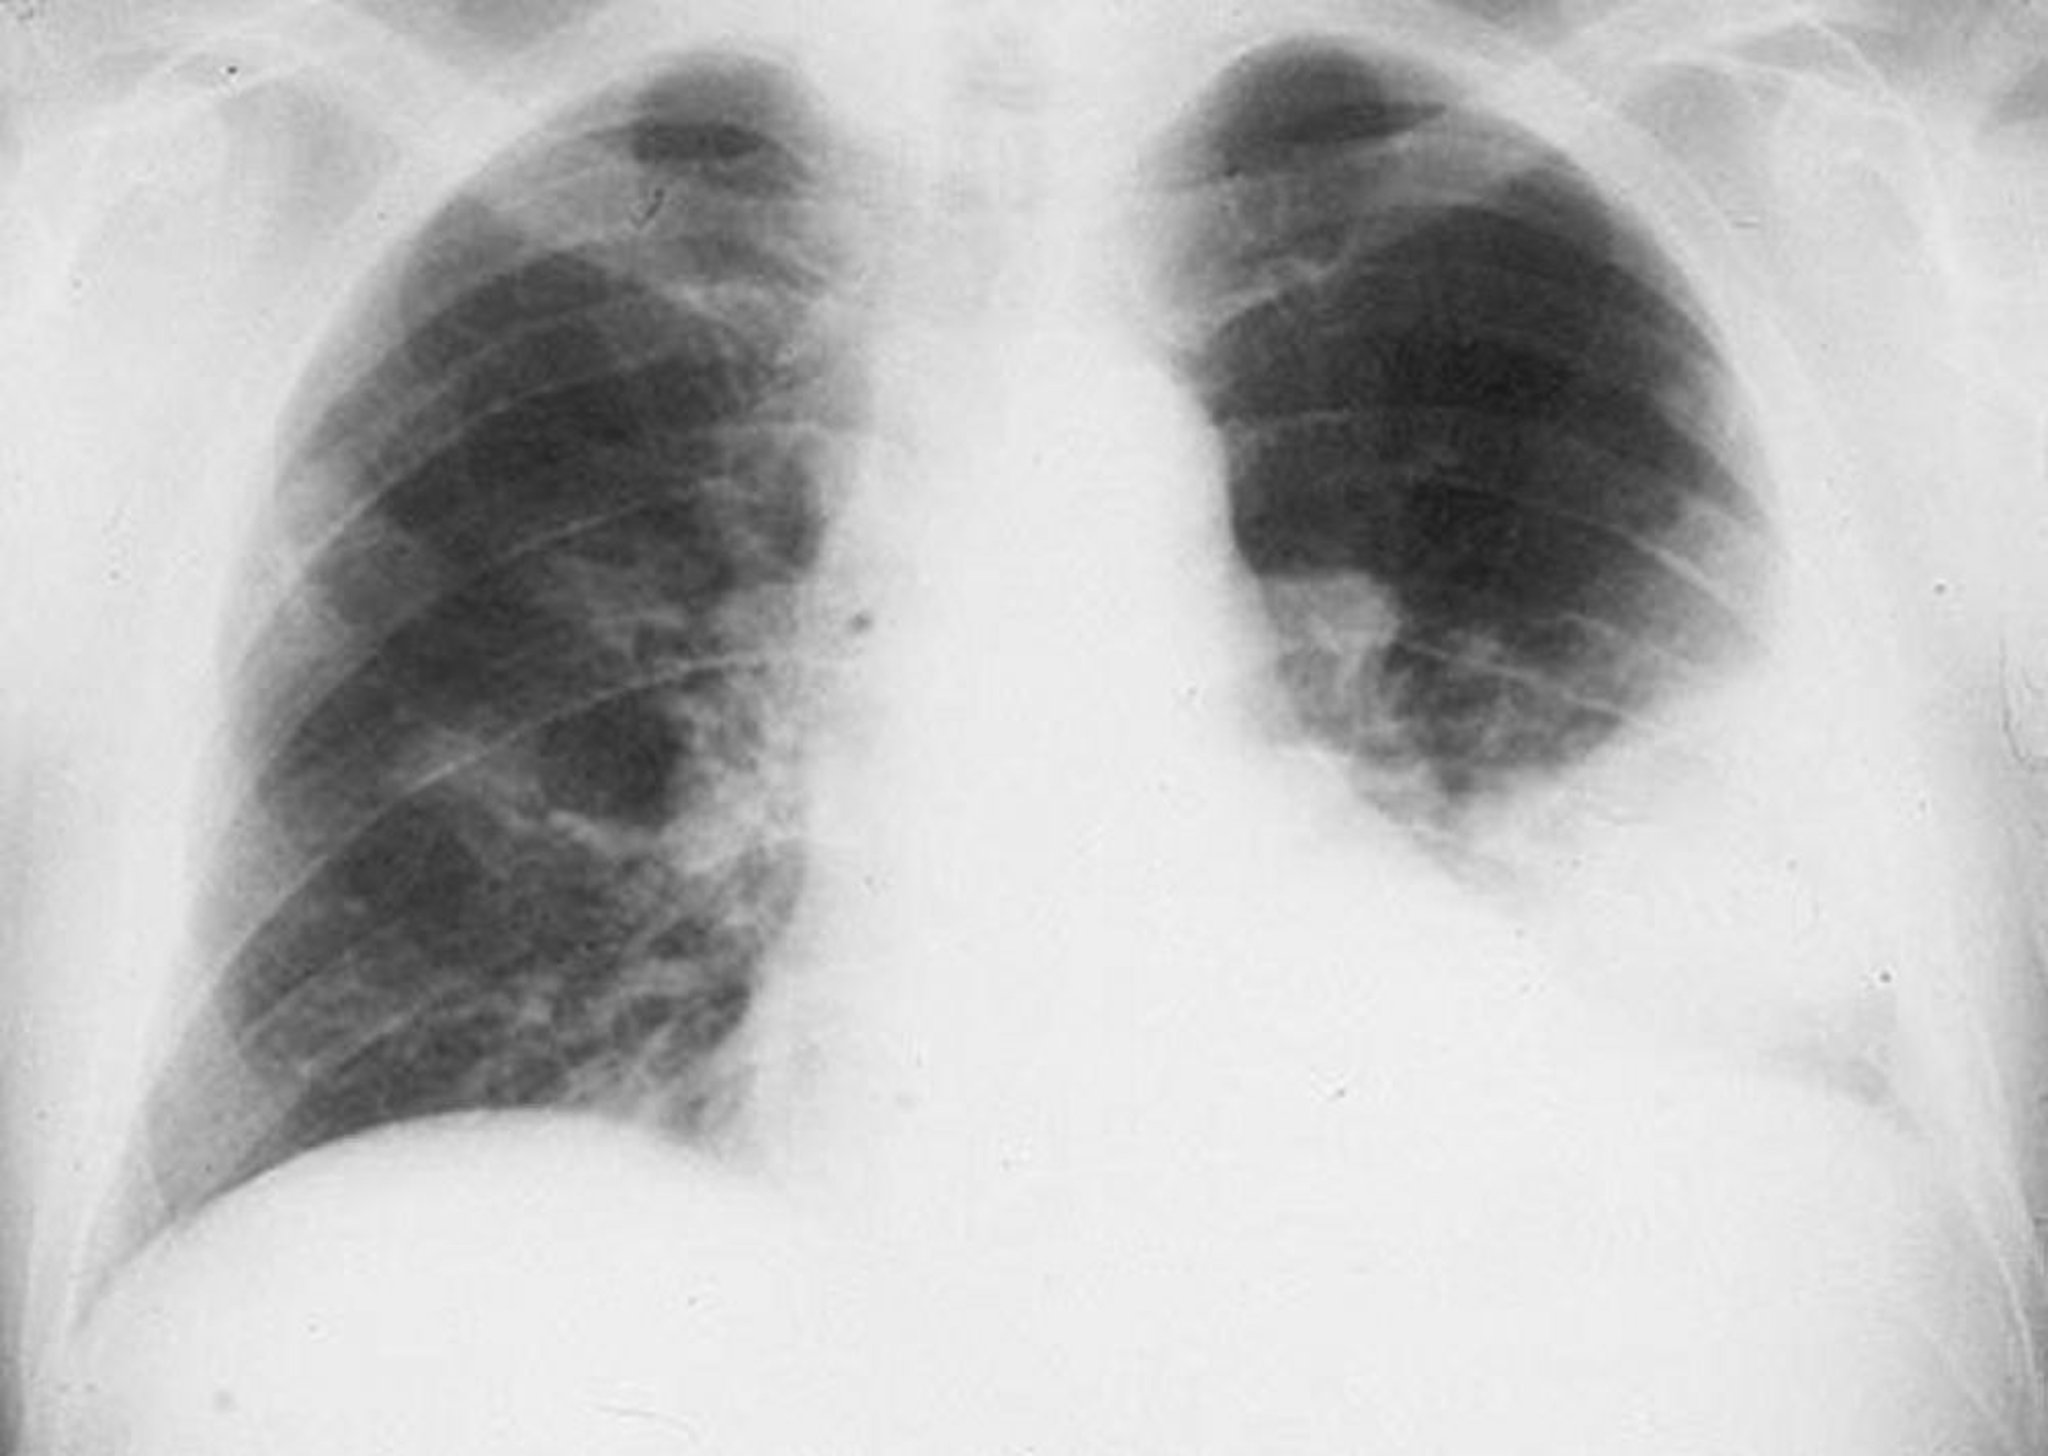

Infiltrat des linken Unterlappens

Alveolares Infiltrat des linken Unterlappens bei einem Mann mit bakterieller Pneumonie.

By permission of the publisher. Von Roberts R. In Atlas of Infectious Diseases: Pleuropulmonary and Bronchial Infections. Herausgegeben von GL Mandell (Serienherausgeber) und MS Simberkoff. Philadelphia, Current Medicine, 1996.